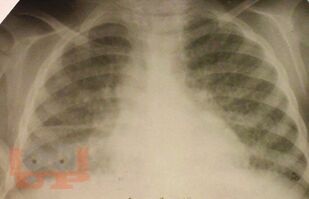

В учебно-методическом пособии отражена характеристика такого инфекционного заболевания как туберкулез, которое по-прежнему остается серьезной проблемой во всем мире. Дана характеристика основных групп риска развития туберкулеза, так как в группах риска заболеваемость туберкулезом в несколько раз выше, чем среди остальной части населения Российской Федерации и Ставропольского края. В пособии дано определение состоянию латентной туберкулезной инфекции, и подробно изложены методы ее диагностики. Также отражены основные направления профилактических мероприятий среди всех возрастных категорий, позволяющие снизить напряженность эпидемической ситуации по распространению туберкулеза.